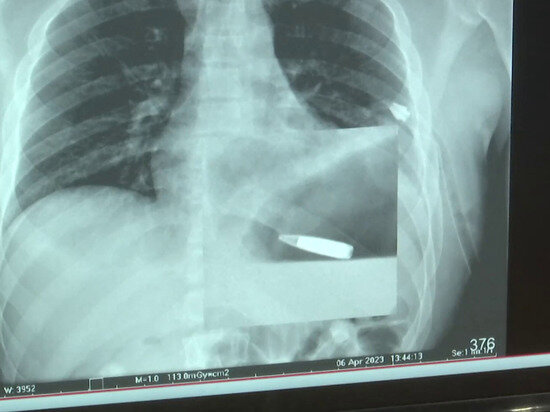

Российские военные медики извлекли пулю из сердца военнослужащего

Кадр из видео